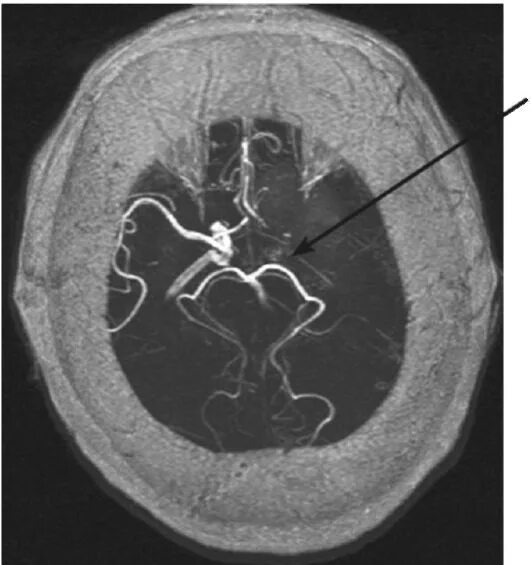

Аневризма головного мозга на кт